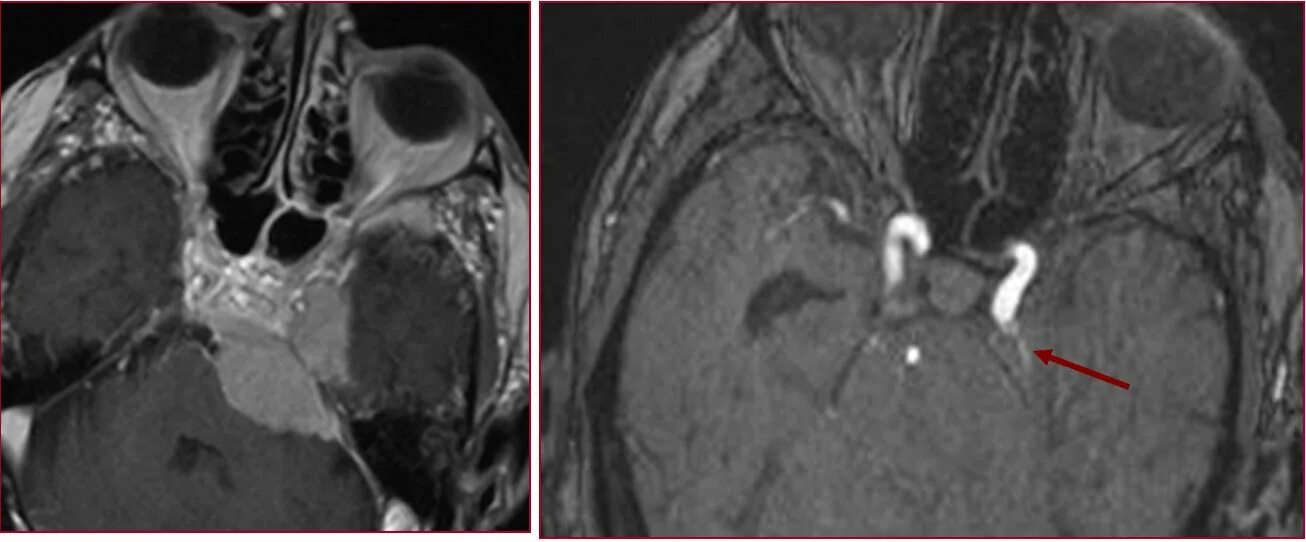

Тромбоз кавернозных